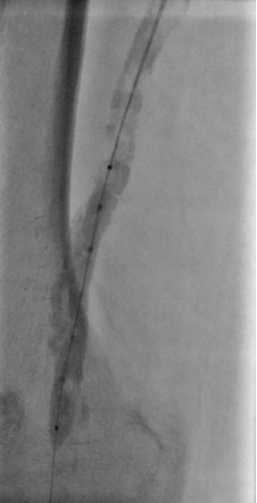

4. 开通胫前-足背动脉

5. 选择6*60mm Shockwave冲击波球囊处理股腘动脉

6. 股浅动脉下段置入6-150mm载药支架,于股浅动脉中上段置入6-220、 6-150mm载药球囊扩张